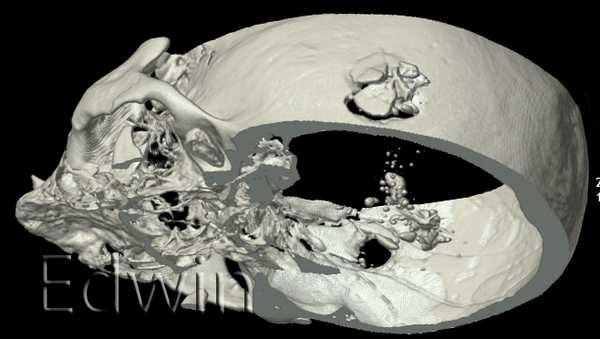

Вырезан виртуальный сегмент плоскости раневого канала. Вид на внутреннюю поверхность правой височной кости со входным огнесрельным дефектом кости и на наружную поверхность левой теменной кости с выходным огнестрельным отверстием.